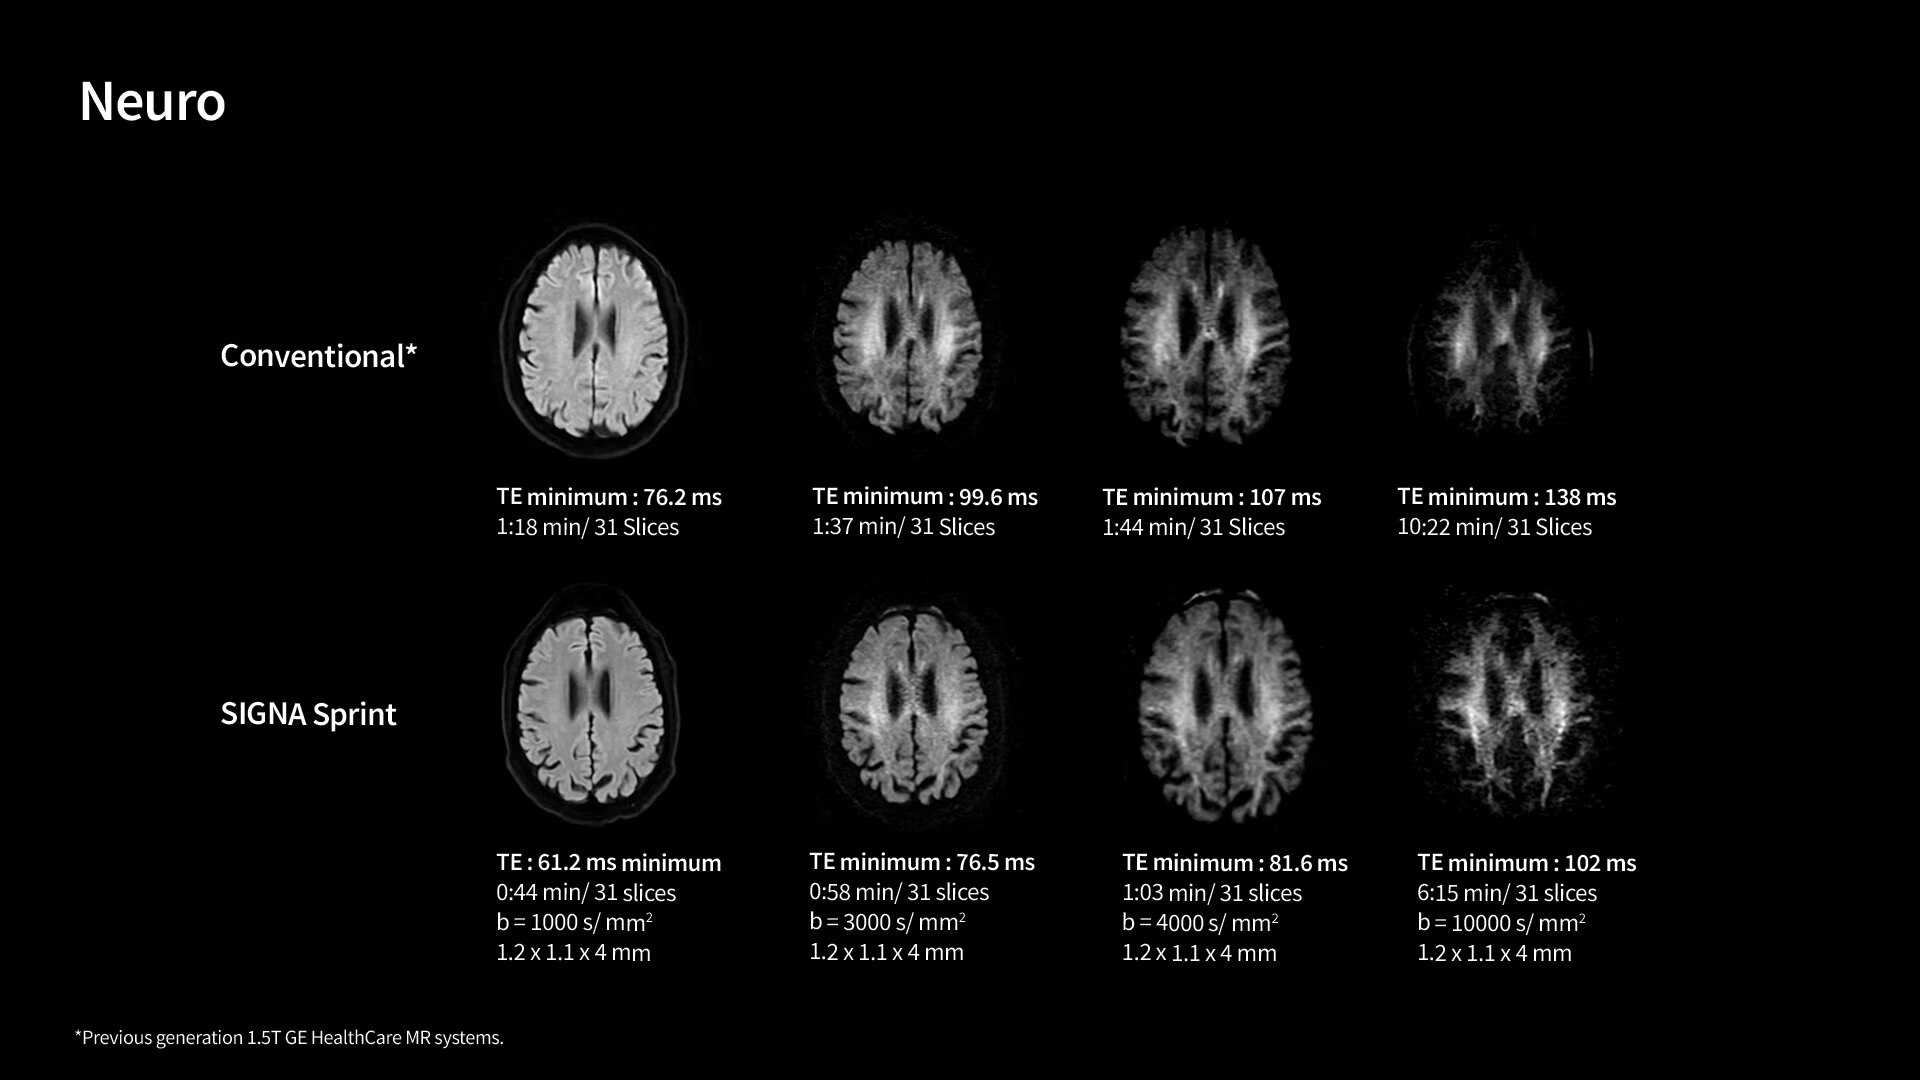

In oncological assessments, diffusion imaging is a critical clinical indicator. SIGNA Sprint offers clearer diffusion, reduced distortion and improved SNR.¹

The growing clinical need within oncology and cardiology requires an MRI scanner that can rise to the challenge. With a high gradient performance of 65/200, SIGNA Sprint helps deliver crystal-clear imaging for ultimate diagnostic confidence. Improved signal-to-noise ratio (SNR) and diffusion, with deep-learning solutions that could enhance diagnostics and treatment response monitoring in your oncology patients.¹ Additionally, the shift from qualitative to quantitative cardiac MRI reduces the time and expertise needed to interpret scans and offers greater consistency and reliability. Helping you to unlock the power to explore further - even in your most challenging cases.

1. Compared to other GE HealthCare legacy systems.